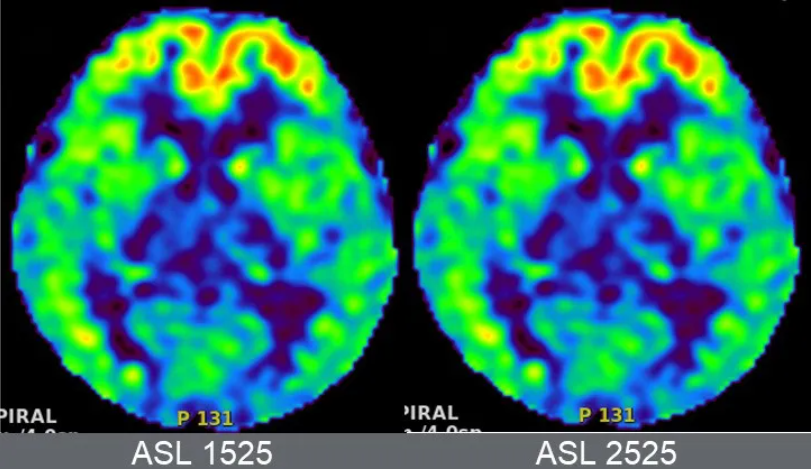

MR三把利器:平扫,增强,结合临床。难道这个病例最后也是结合临床?20210707,第三次MR检查;3D ASL提示,双侧额叶灌注增加